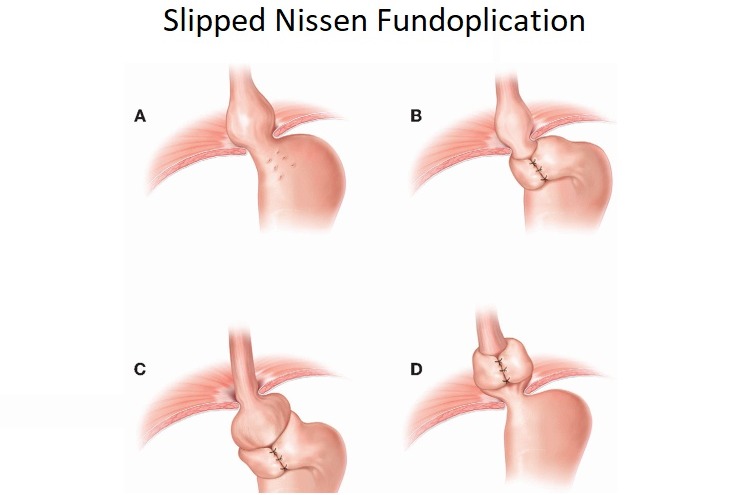

Back in January 2004 I was diagnosed with a large Hiatal Hernia with extreme GERD I then had a laparoscopic Nissen Fundoplication to try and repair this. After the surgery I still felt the sliding up and down motion and found it hard to breathe. I then went back to the surgeon that repaired it and he said it was fixed. I knew It wasn’t right, so I went and searched for other doctors. I found a doctor out of state and he also said I did not have a Hiatal Hernia. I told him I had “A knocking below my sternum” and so he removed half of it this left a Ventral and Incisional Hernia and I still felt an up and down motion leaving me extremely short of breath. I then found another G.I. doctor who found the problem. I had a large Sliding Hiatal Hernia at the 35cm at the E.G. Junction with the Nissen intact. He referred me to a surgeon who confirmed a Ventra Hernia with many adhesions. He never repaired the Hiatal Hernia, but the mesh and adhesion removal helped, and I’ve been functional for 14 years. However, I started working at a wholesale club where I had to twist and bend while lifting heavy things. At the same time, I contracted Bronchitis and I coughed a lot and gagged. I felt something pop and then all my symptoms began. I was able to get a surgeon right a way who did a CAT Scan. The CAT Scan showed a large Ventral and Abdominal Wall Hernia. My stomach, liver, and intestines were protruding outside my Ventral and abdominal wall. The next day they performed emergency surgery. I had my original paperwork from 2004 but they refused to see it. They opened me up and put mesh in the Ventral and Abdominal Wall. This seem to only make my breathing and sliding of my Hiatal Hernia worse. They said I did not have/ did not see a Hiatal Hernia. This seems impossible because they don’t just magically disappear. A week and a half post-surgery every time I breathe or talk it feels like my stomach is moving up and down and slamming into the mesh they placed in the Ventral area. I am unable to eat, sleep, or breath very well. I do not have any quality of life because I am too out of breath and this big bulge comes up when I breathe. I have told them of my symptoms, but the surgeon says he will not do anything until the surgery heals. I feel helpless and feel with every breathe I am going to die. I can’t eat so I am very weak. I need help fast and I don’t know what to do.

A life saving operation was performed recently and solved a Ventral Hernia and Abdominal Wall Hernia but Nissen Fundiplocation/Hiatal Hernia was untouched and unacknowledged which amounts to 100,000.00 just for initial charge not including hospital stay and any other various charges here soon. Unheased the liver, stomach, intestines, as they we intertwined. Which is why immediate Life-Threatening surgery was performed. We were discharged with 4 tubes still in the stomach area and staples from sternum through/ 1 inch past the belly button which makes maintenance a continuous 24/7 task to keep sanitary along with medications, contacting agencies such as Human Arc, following up with Medicare, find a doctor in the area willing to acknowledge and re-operate to solve the Nissen Fundoplication soon as we wait a second week to remove the 4 tubes. This has made every second of every day uncertain and continually asking what is right? Who do we see? What is next? Why must every waking second be difficulty and pain? Every minute has counted. Post-Op symptoms include but are not limited to: Further problem breathing, new mesh feels displaced and is rather large, and severe acid reflux preventing most solid foods, on and off numbness of the stomach area. Thus far she has been restrained to night shirts, mostly sitting and laying flat down, and inability to be seen/managed publicly and hindering day-to-day activities.

Back in January 2004 I was diagnosed with a large Hiatal Hernia with extreme GERD I then had a laparoscopic Nissen Fundoplication to try and repair this. After the surgery I still felt the sliding up and down motion and found it hard to breathe. I then went back to the surgeon that repaired it and he said it was fixed. I knew It wasn’t right, so I went and searched for other doctors. I found a doctor out of state and he also said I did not have a Hiatal Hernia. I told him I had “A knocking below my sternum” and so he removed half of it this left a Ventral and Incisional Hernia and I still felt an up and down motion leaving me extremely short of breath. I then found another G.I. doctor who found the problem. I had a large Sliding Hiatal Hernia at the 35cm at the E.G. Junction with the Nissen intact. He referred me to a surgeon who confirmed a Ventra Hernia with many adhesions. He never repaired the Hiatal Hernia, but the mesh and adhesion removal helped, and I’ve been functional for 14 years. However, I started working at a wholesale club where I had to twist and bend while lifting heavy things. At the same time, I contracted Bronchitis and I coughed a lot and gagged. I felt something pop and then all my symptoms began. I was able to get a surgeon right a way who did a CAT Scan. The CAT Scan showed a large Ventral and Abdominal Wall Hernia. My stomach, liver, and intestines were protruding outside my Ventral and abdominal wall. The next day they performed emergency surgery. I had my original paperwork from 2004 but they refused to see it. They opened me up and put mesh in the Ventral and Abdominal Wall. This seem to only make my breathing and sliding of my Hiatal Hernia worse. They said I did not have/ did not see a Hiatal Hernia. This seems impossible because they don’t just magically disappear. A week and a half post-surgery every time I breathe or talk it feels like my stomach is moving up and down and slamming into the mesh they placed in the Ventral area. I am unable to eat, sleep, or breath very well. I do not have any quality of life because I am too out of breath and this big bulge comes up when I breathe. I have told them of my symptoms, but the surgeon says he will not do anything until the surgery heals. I feel helpless and feel with every breathe I am going to die. I can’t eat so I am very weak. I need help fast and I don’t know what to do.

A life saving operation was performed recently and solved a Ventral Hernia and Abdominal Wall Hernia but Nissen Fundiplocation/Hiatal Hernia was untouched and unacknowledged which amounts to 100,000.00 just for initial charge not including hospital stay and any other various charges here soon. Unheased the liver, stomach, intestines, as they we intertwined. Which is why immediate Life-Threatening surgery was performed. We were discharged with 4 tubes still in the stomach area and staples from sternum through/ 1 inch past the belly button which makes maintenance a continuous 24/7 task to keep sanitary along with medications, contacting agencies such as Human Arc, following up with Medicare, find a doctor in the area willing to acknowledge and re-operate to solve the Nissen Fundoplication soon as we wait a second week to remove the 4 tubes. This has made every second of every day uncertain and continually asking what is right? Who do we see? What is next? Why must every waking second be difficulty and pain? Every minute has counted. Post-Op symptoms include but are not limited to: Further problem breathing, new mesh feels displaced and is rather large, and severe acid reflux preventing most solid foods, on and off numbness of the stomach area. Thus far she has been restrained to night shirts, mostly sitting and laying flat down, and inability to be seen/managed publicly and hindering day-to-day activities.